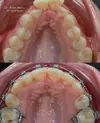

Diş Çapraşıklığı